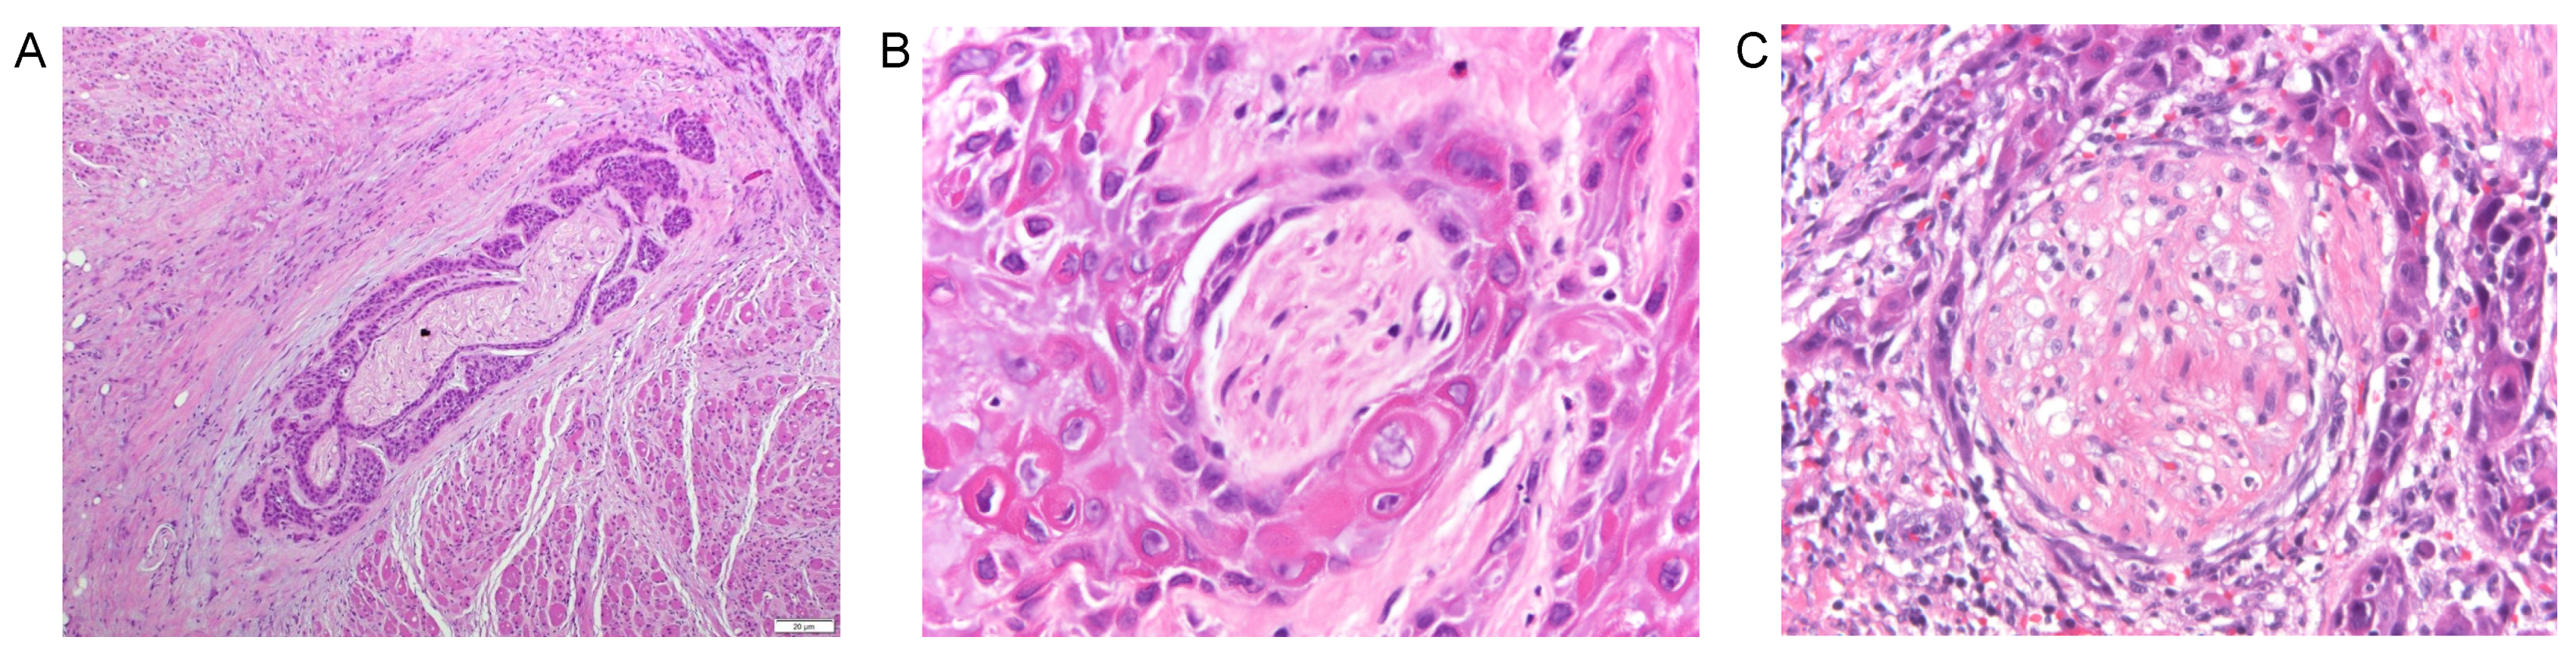

3. Definitions for Perineural Invasion (PNI)

5.1. Cellular Observations in Perineural Invasion

- Varsha, B.K.; Radhika, M.B.; Makarla, S.; Kuriakose, M.A.; Kiran, G.S.; Padmalatha, G.V. Perineural invasion in oral squamous cell carcinoma: Case series and review of literature. J. Oral Maxillofac. Pathol. 2015, 19, 335–341. [Google Scholar] [CrossRef]